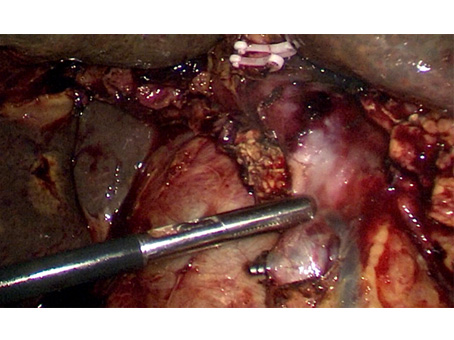

We have state of the art operating theatre with advanced surgical equipments. We have a Karl Storz Spies advanced HD laparoscopy operating system in addition to a 3 chip laparoscopy. We have installed advanced vessel sealing devices like Gen 11 harmonic scalpel, Ligasure from Valley Lab & Argon plasma coagulator. There is a recent addition of Cavitron Ultrasonic Aspirator (CUSA) system into our surgical armamentarium. We have the most recent powered Echelon endo-stapling devices. In addition to all these we have a constant supply of various types of advanced stapling devices for GI surgeries. Our endoscopy machines are having high definition with FICE Technology. Last but not the least we have semi flexible Ureteroscopy for managing common bile duct stones.

CAVITRON ULTRASONIC ASPIRATOR USED FOR LIVER RESECTION

LIVER RESECTION DONE USING CUSA